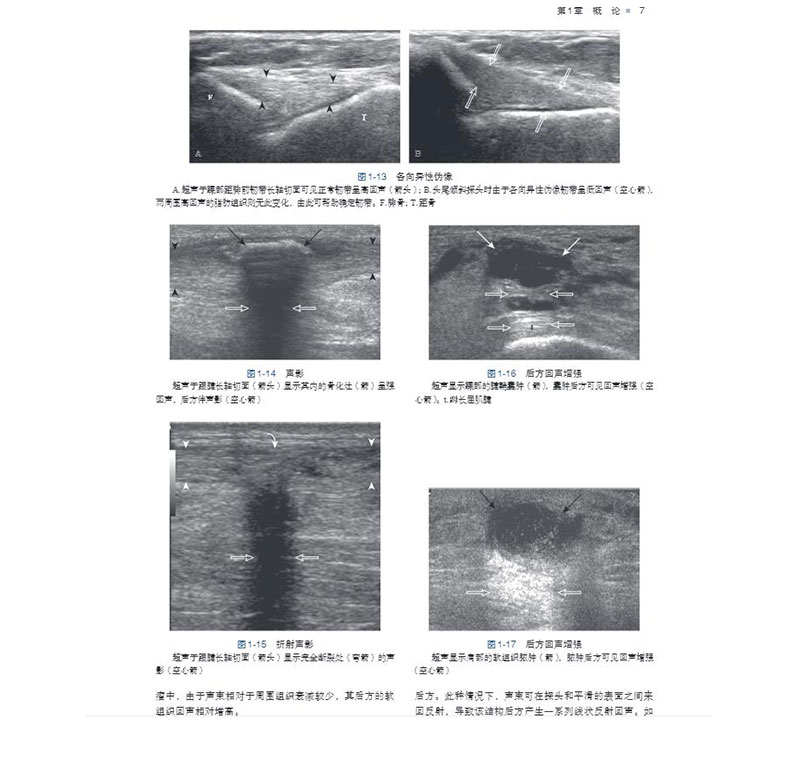

五、超声伪像5